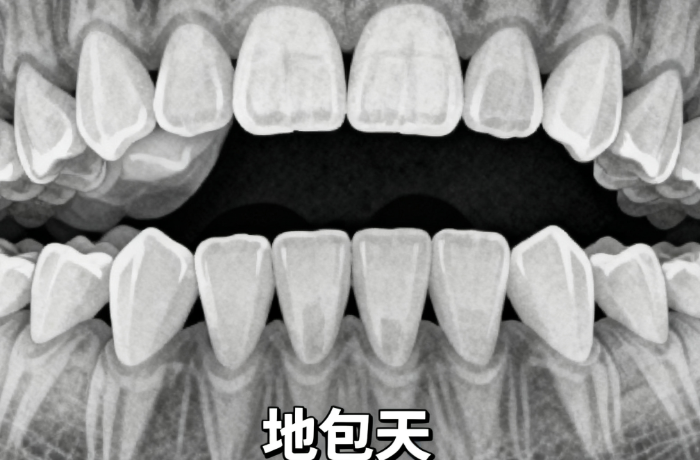

1、力学原理:柯帝夫托槽主要是通过施加适当的力量来引导牙齿移动。托槽与弓丝相互配合,弓丝的弹性形变会产生一定的力量,这种力量传递到托槽上,进而作用于牙齿。牙齿在这种持续的力量作用下,会逐渐发生移动,较终达到矫正的目的。

2、生物学原理:牙齿周围的牙槽骨具有一定的可塑性。当托槽施加力量时,牙槽骨会发生改建。在受力的一侧,牙槽骨会逐渐吸收,而在另一侧则会有新的骨质形成。通过这种牙槽骨的改建过程,牙齿能够在新的位置上稳定下来,实现牙齿的矫正。www.5#*9w.net